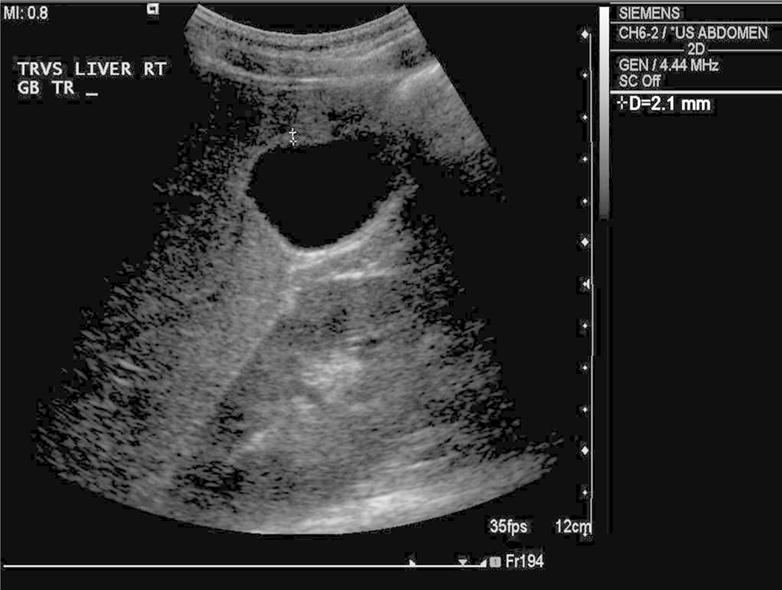

Figure 3.

Transverse grayscale ultrasound of the gallbladder 7 days after admission demonstrates resolved gallbladder wall thickening (calipers), now measuring 2.1 mm, within normal range.